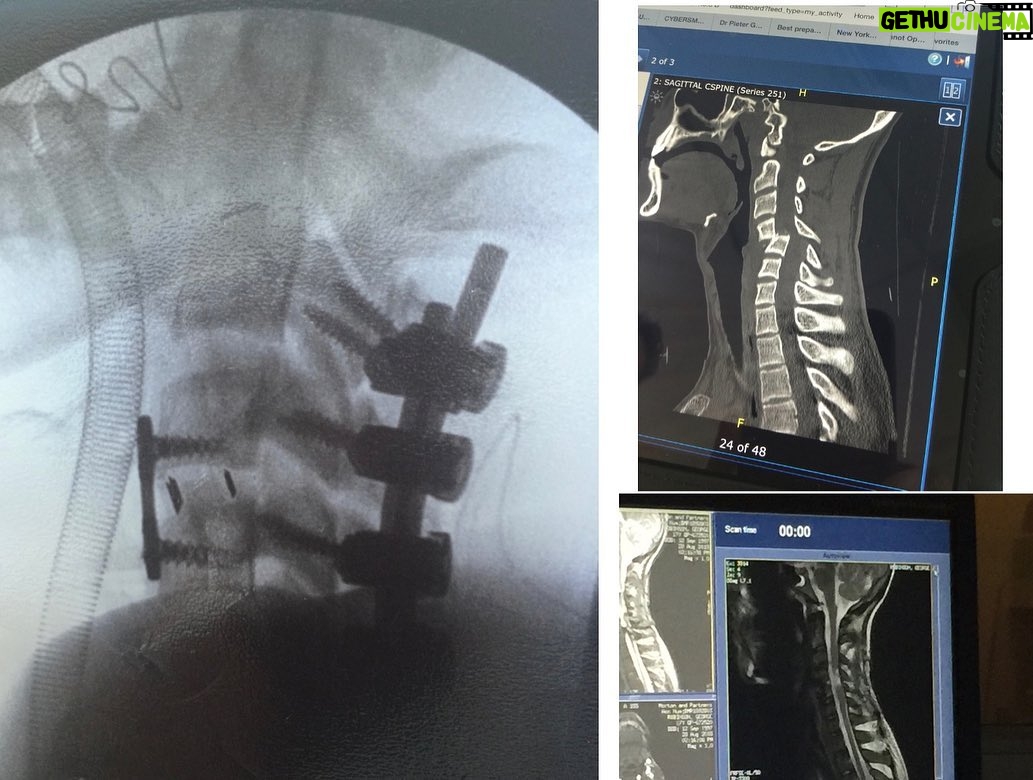

55.7K Likes – George Robinson Instagram

Caption : 9 years ago, I broke my neck. 15 years ago, I stubbed my toe. 20 years ago, I lost my favourite toy car. Trauma can always be overcome.Likes : 55736

55.7K Likes – George Robinson Instagram

Caption : 9 years ago, I broke my neck. 15 years ago, I stubbed my toe. 20 years ago, I lost my favourite toy car. Trauma can always be overcome.Likes : 55736

55.7K Likes – George Robinson Instagram

Caption : 9 years ago, I broke my neck. 15 years ago, I stubbed my toe. 20 years ago, I lost my favourite toy car. Trauma can always be overcome.Likes : 55736

48.4K Likes – George Robinson Instagram

Caption : Five years ago today I broke my neck. Silly me LOLLikes : 48440

48K Likes – George Robinson Instagram

Caption : eight years ago, I realised that standing up was overrated thanks to everyone who has helped and followed me on this weird journey.Likes : 48016

48K Likes – George Robinson Instagram

Caption : eight years ago, I realised that standing up was overrated thanks to everyone who has helped and followed me on this weird journey.Likes : 48016

47.3K Likes – George Robinson Instagram

Caption : seven years ago today, I broke my neck it seems to have been a good career move in hindsightLikes : 47251

47.3K Likes – George Robinson Instagram

Caption : seven years ago today, I broke my neck it seems to have been a good career move in hindsightLikes : 47251